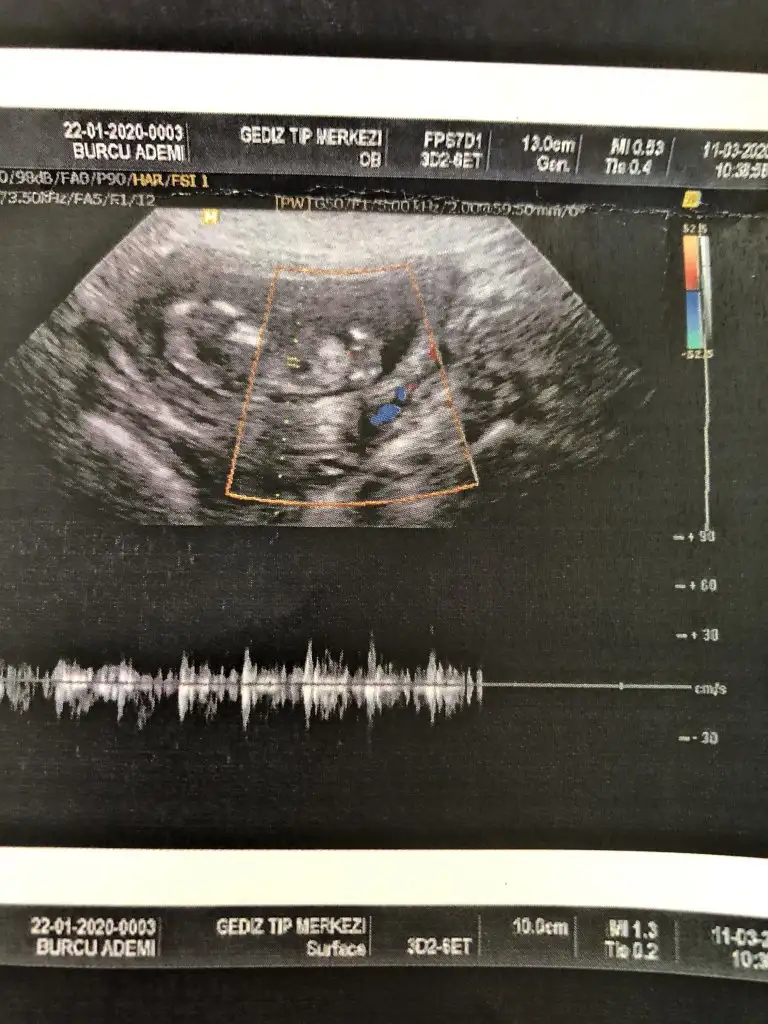

Ikra meyra canim bakar mısın Bi cinsiyet tahmini 15 haftalık

Kız gibielimdeki tüm usg görüntüleri bunlaryeterli olur mu ki tahmin için